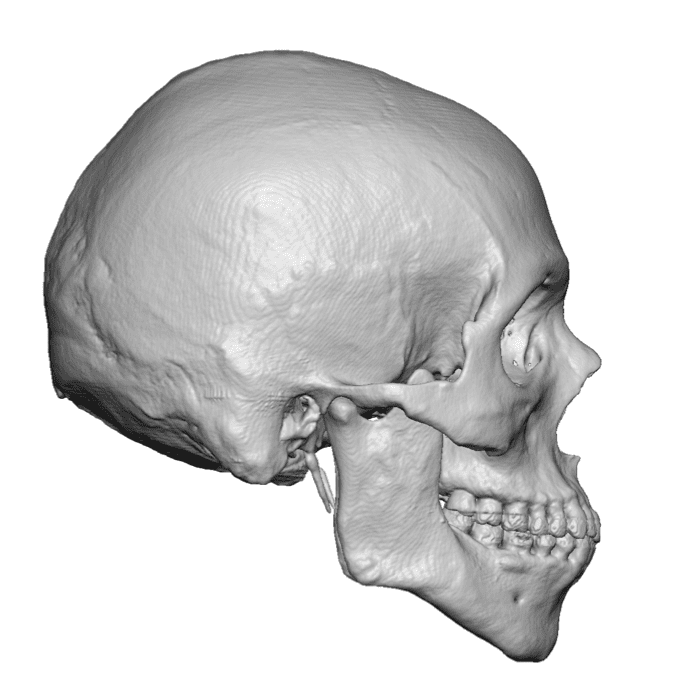

Desire for a higher and more prominent crown of the skull.

Crown of skull augmentation using a custom skull implant.

Desire for a higher and more prominent crown of the skull.

Crown of skull augmentation using a custom skull implant.